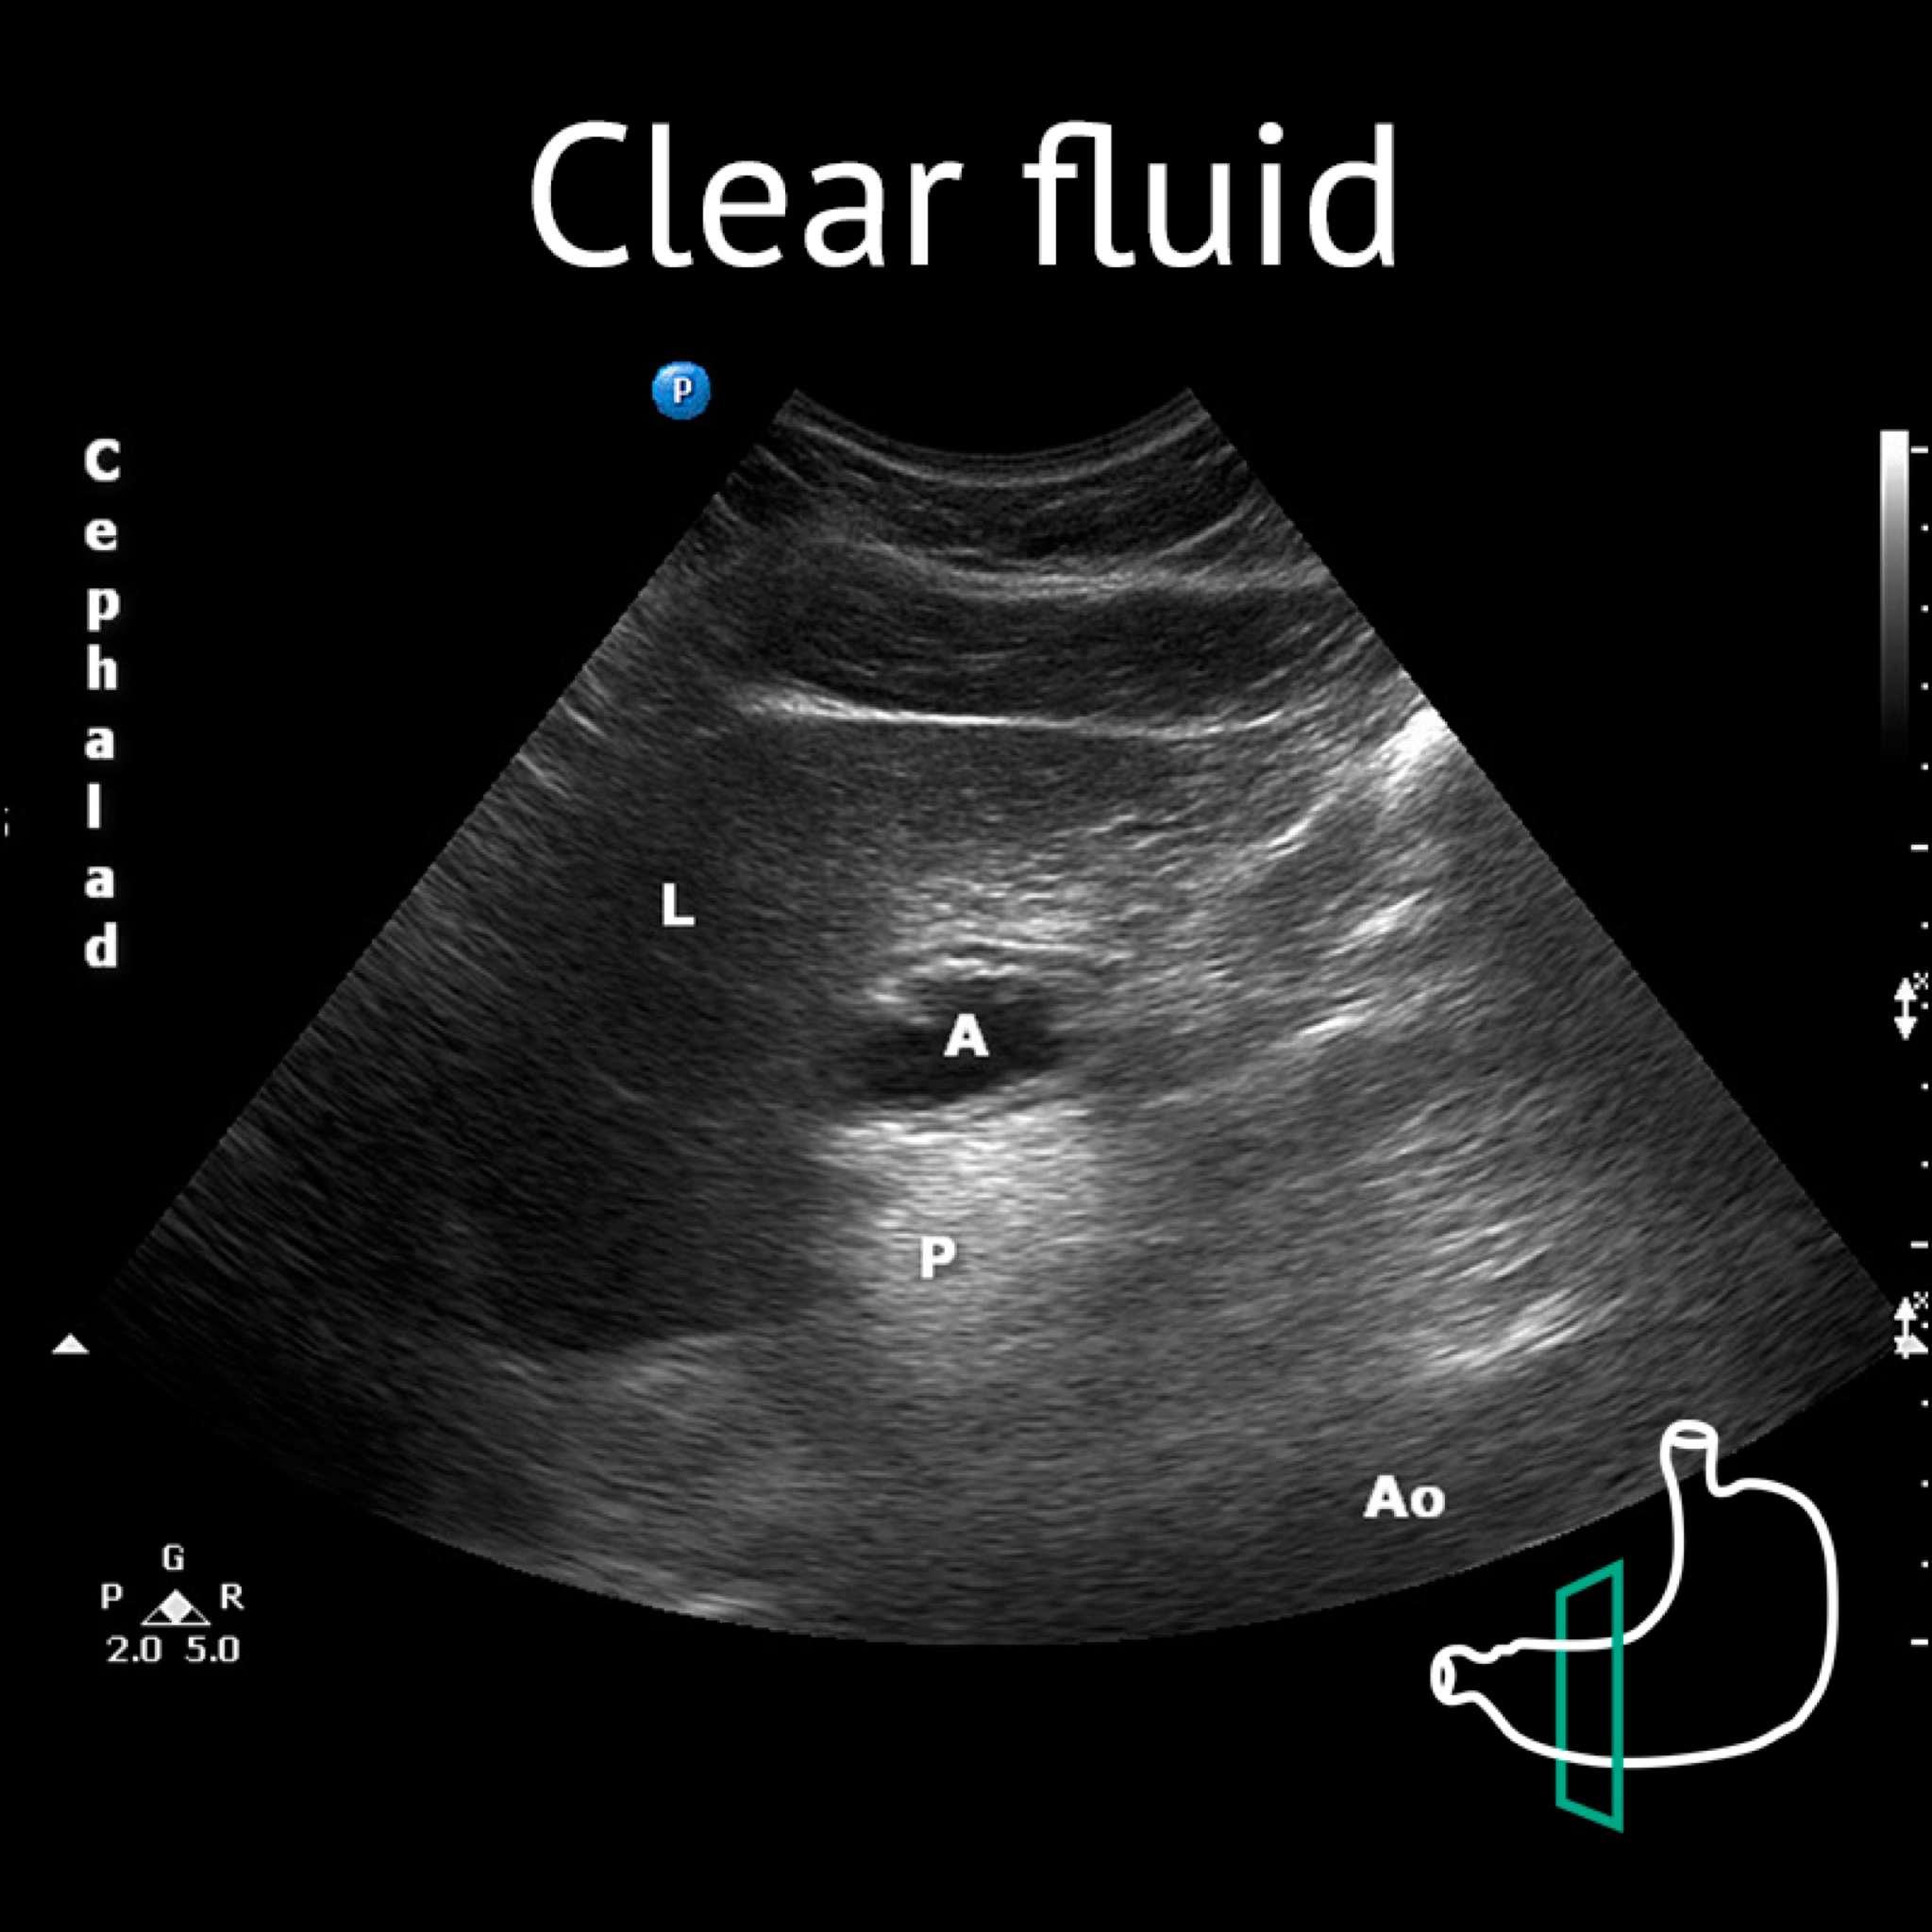

A: antrum; Ao:aorta; L: liver; P: pancreas